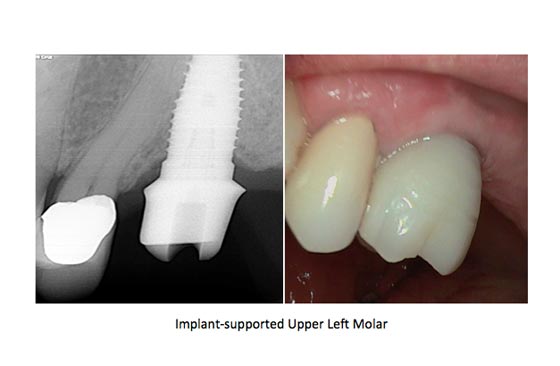

- Dental Implants